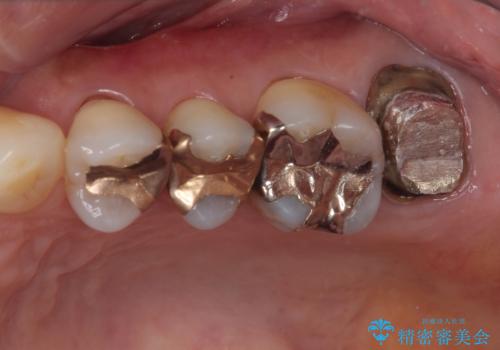

- 被せものに穴が開いたとのことで来院された患者様です。被せものをやり替えることになったので、かみ合わせが強い方のでPGAクラウンをご提案しましたが患者様の強いご希望によりオールセラミッククラウンによる補綴治療を行っていくことになりました。

拡大鏡視野下で、金属の被せもの、虫歯の除去を行い、オールセラミッククラウンに適した形に整えました。